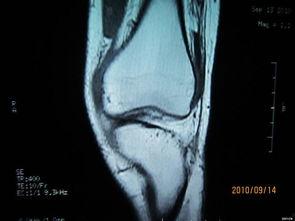

首先,得弄明白什么是膝关节积液。简单来说,就是关节腔内多了一些不该有的液体。这些液体可能是由于关节损伤、炎症、感染等原因造成的。当关节腔内液体过多时,就会导致关节肿胀、疼痛,甚至影响正常活动。

那么,如何解决这个烦恼呢?这时候,膝关节积液抽水手术就派上用场了。这个手术听起来有点吓人,但其实就是一个简单的操作过程。

首先,医生会在你的膝关节上做一个小的切口。别担心,这个切口很小,恢复起来也很快。医生会插入一根细长的针,通过这个针将多余的液体抽出来。这个过程可能会有些疼痛,但医生会给你打麻药,所以你不用担心。